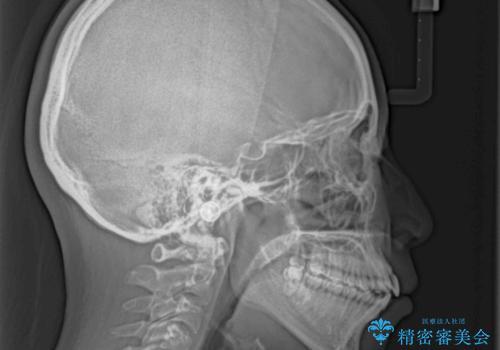

飛び出した上顎前歯 抜歯矯正で横顔の印象を改善

強い舌の突出癖により、上下前歯が前方に飛び出しており、特に上顎前歯は下顎よりも更に前方に位置している状態でした。

上顎前歯をしっかりと後方に移動させるため、口蓋側にアンカースクリューと補助装置を併用し、上下左右の第一小臼歯4本を抜歯し、ワイヤー装置にて矯正治療を行うこととしました。